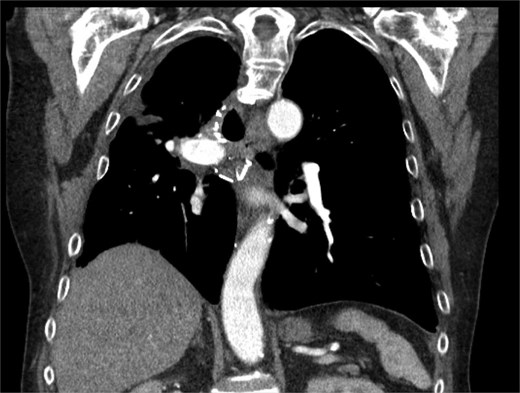

Subsequently the patient showed clinical and radiographic improvement, allowing pleural catheter removal. Surveillance CT scans at 2 and 6 months after hospitalization showed a decrease in the size of the intrapleural abscess without malignant recurrence (Fig. 2).

CT chest at 6 months with contrast with trace loculated pleural effusion and improved consolidation.